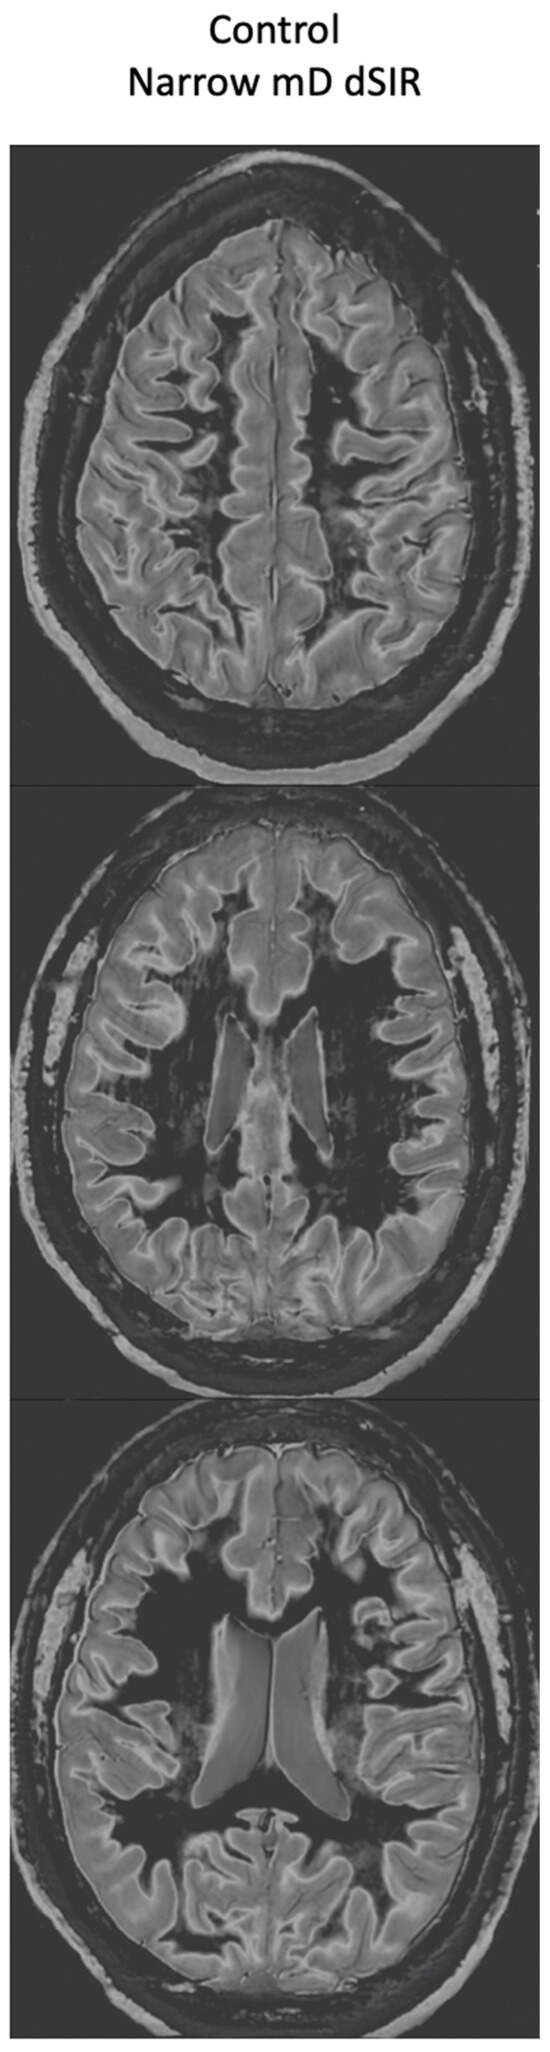

Figure 17, left column shows narrow mD dSIR images from the 50-year-old normal control (left column) and from the patient at his initial MR examination after one month’s abstinence. The normal control shows a very low signal (dark) appearance in most of his white matter. There is an intermediate signal and higher signal in and around the corticospinal tracts (whiteout sign grade 1). In the right column, the patient’s white matter shows extensive areas of high signal with only small areas of more normal lower signal white matter present in the periphery (white arrows) (whiteout sign grade 4).

Figure 17.

A 50-year-old normal control (left column) and Case 1, a 51-year-old with methamphetamine use disorder (right column). 2D dSIR narrow mD images are shown. The narrow mD dSIR images in the normal control show most white matter as very low signal intensity (dark) with a mid gray and lighter appearance in and around the corticospinal tracts, i.e., whiteout sign grade 1. The narrow mD dSIR images in the patient show widespread high signal changes in white matter with only small areas of normal dark white matter at the periphery of the white matter (white arrows). The features are consistent with a whiteout sign grade 4. Normal high signal boundaries are seen between white matter and gray matter on the dSIR images in the control and the patient, but are less obvious in the patient because of the high signal in his abnormal white matter.

There is a dramatic difference between normal white matter on the left which is black and abnormal white matter on the right which is white (apart from small spared or relatively spared areas).